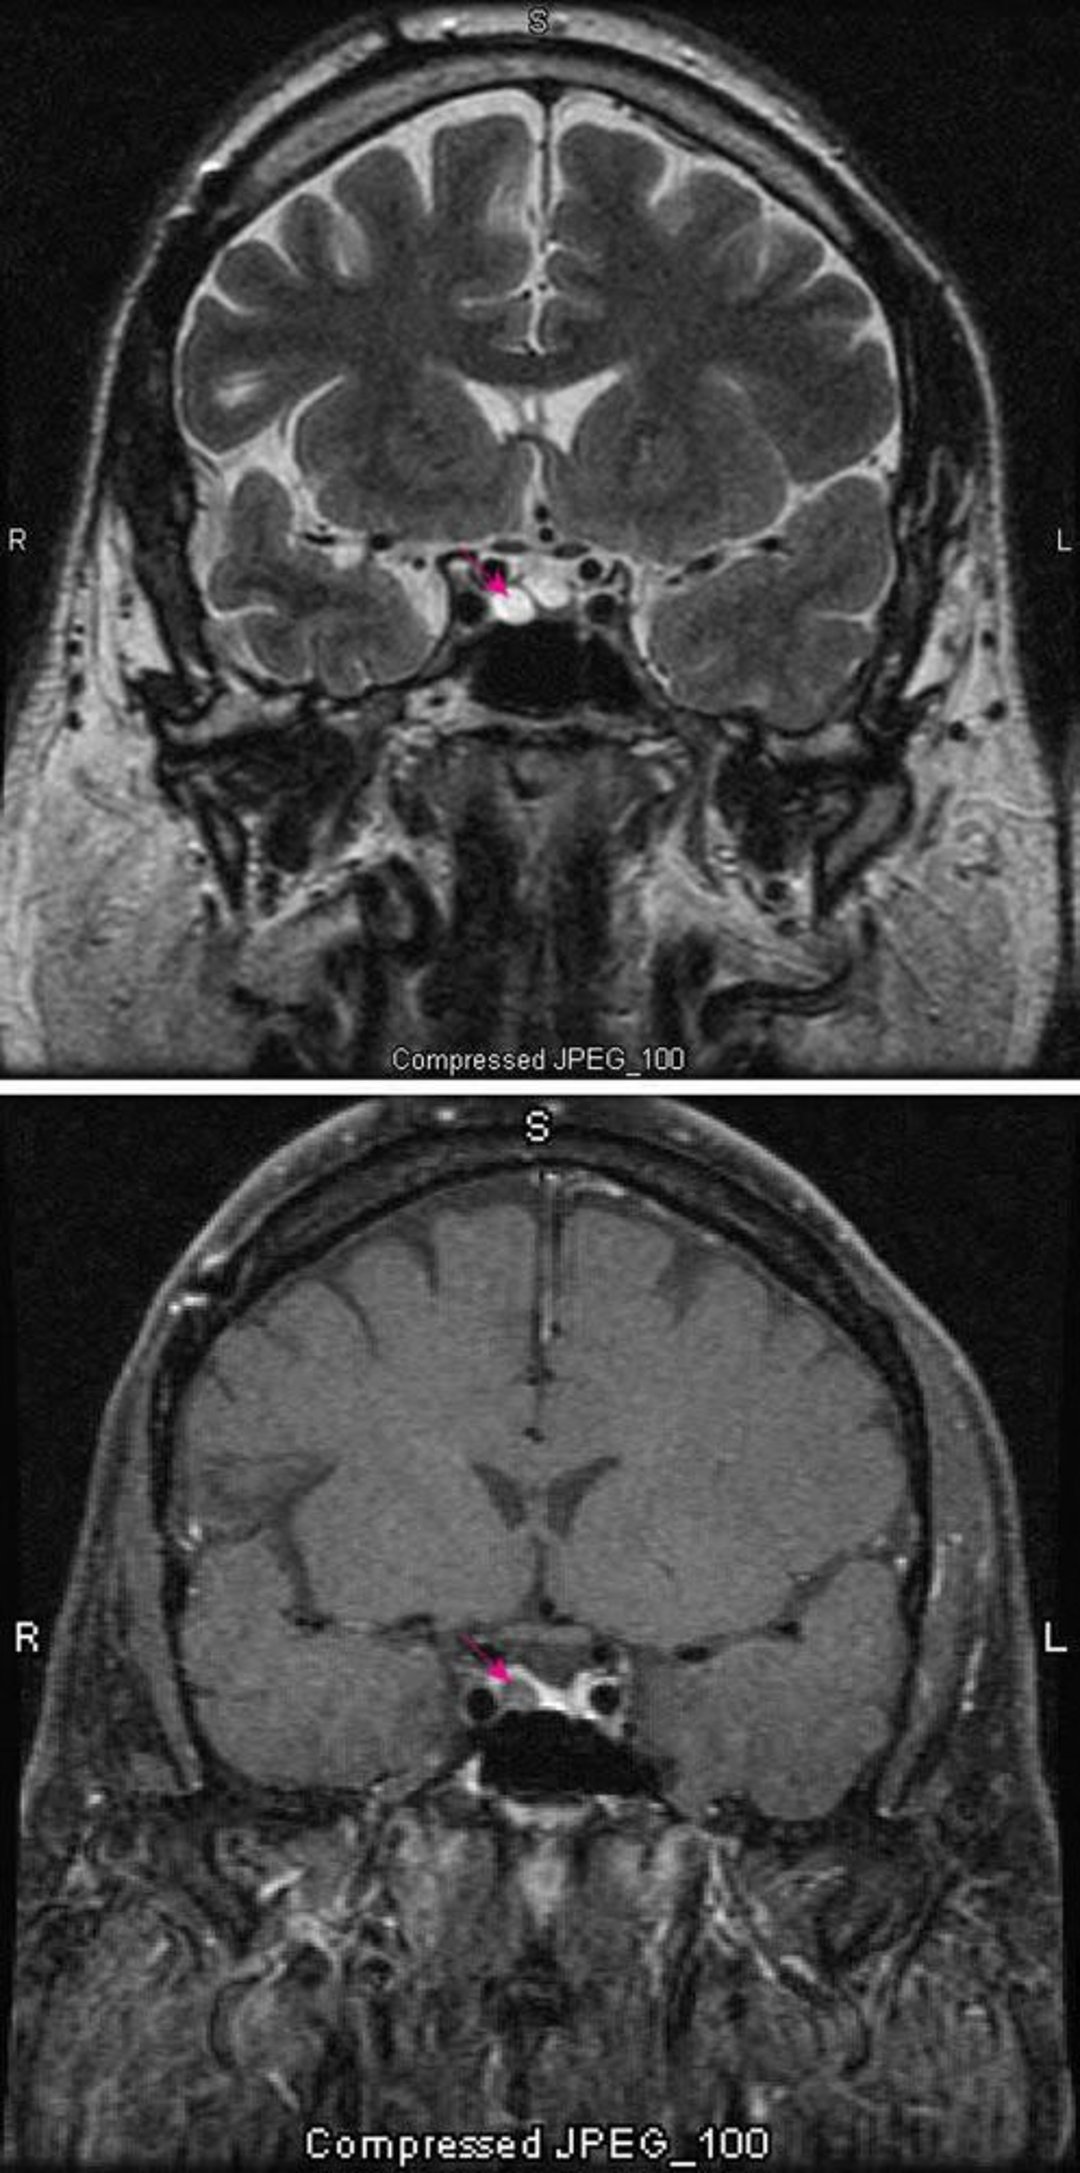

下垂体微小腺腫

MRIのT2強調画像(上)には,下垂体微小腺腫(赤矢印)が認められる。造影すると(下),正常なら下垂体が増強される(赤矢印)。腺腫はより明るく描出される。

Images courtesy of William R.Shapiro, MD.